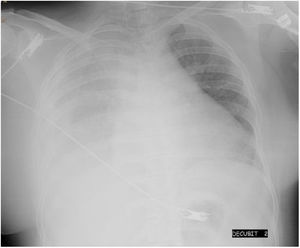

We present the case of a 24-year-old woman with chronic renal failure due to IgA mesangial nephropathy on continuous ambulatory peritoneal dialysis for one month, who was transferred to the emergency department due to intense headache and blurred vision with subsequent loss of consciousness and generalised tonic-clonic movements while undergoing PD replacement. Her previous medical history also included obesity, with a BMI of 32, and hypertension controlled with enalapril and furosemide. The patient subsequently suffered two more episodes of seizures and her blood pressure (BP) was 260/112 mmHg and O2 saturation 87%. The recent history reported by the family included a decrease in peritoneal drainage balances and right rib pain for 2–3 days, and worse control of her BP with values of 165/100 mmHg. She was initially received oxygen therapy, intravenous labetalol, clonazepam and levetiracetam, with a gradual decrease in blood pressure. Further tests included a chest X-ray, showing massive right pleural effusion (Fig. 1), blood tests, showing electrolytes to be normal, normal brain CT scan, lumbar punction with no evidence of infection and eye fundi with preserved macula in both eyes, with no exudates or haemorrhages suggestive of hypertensive retinopathy. Analysis of the pleural fluid was compatible with transudate, with glucose levels higher than plasma blood glucose. With the diagnosis of a massive right pleuroperitoneal leak and given the severity of the patient's clinical condition, a right jugular catheter was inserted and haemodialysis with progressive ultrafiltration started, with recovery of consciousness, gradual decrease in pleural effusion and optimisation of BP control. MRI of the brain at 24 h showed lesions compatible with PRES. Ten days later, a peritoneal scintigraphy showed, 90 min after administration of the radiotracer, diffuse passage of the radiotracer to the right posterior pleural region, occupying a large part of the right thoracic region and causing the patient right pleuritic pain and dyspnoea. We decided to definitively discontinue the PD.